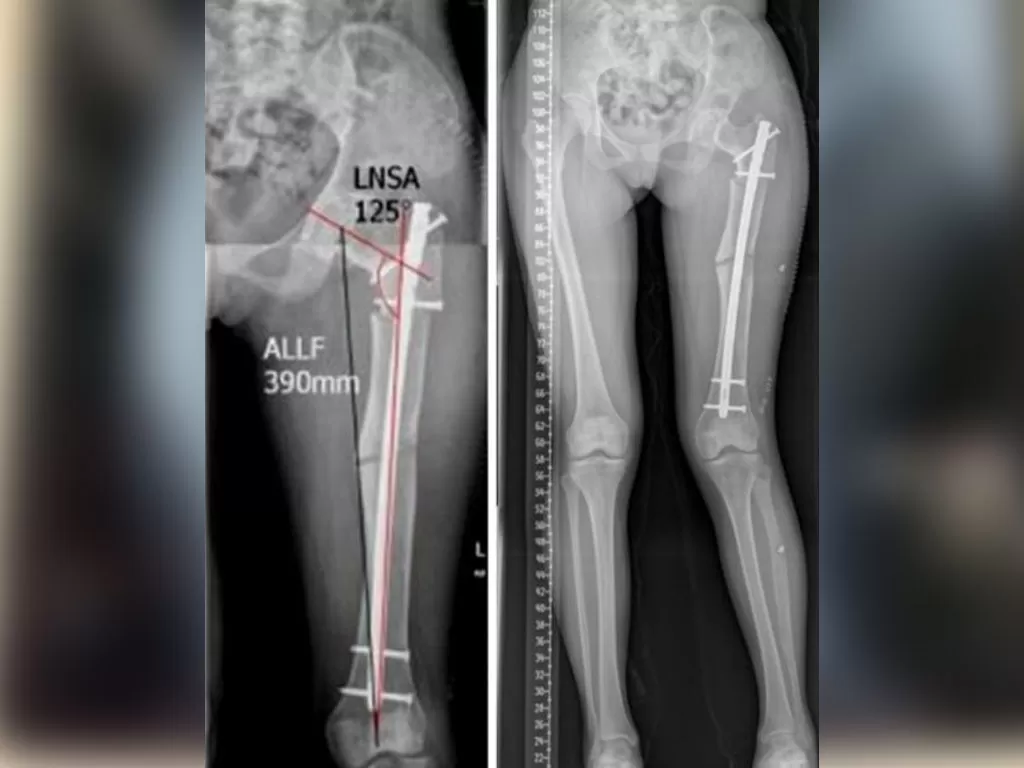

Mr. Abish

Name: Mr. Abish

Date of Operation: 23 Aug 2020

Age: 14 Years